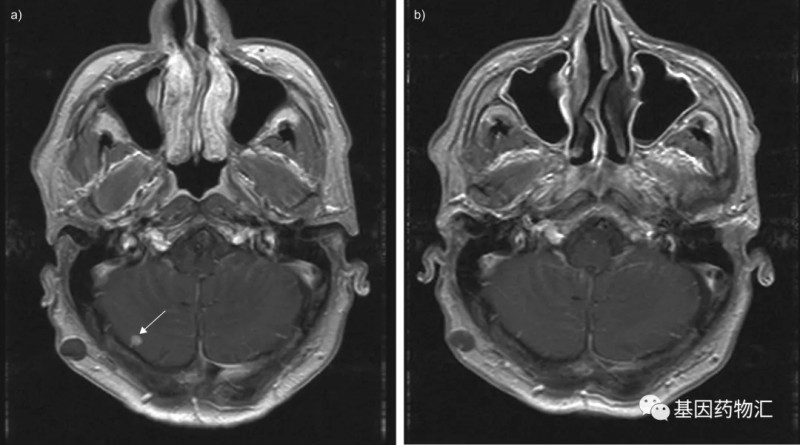

肺癌脑转移就走到了生命的尽头?"头"等大事不容含糊!这些治疗

肺癌脑转移就走到了生命的尽头?"头"等大事不容含糊!这些治疗发布时间:2022-05-07    作者:小编

从生存期上来说,脑转移患者的生存期在各类转移部位的患者当中也是比较差的。...